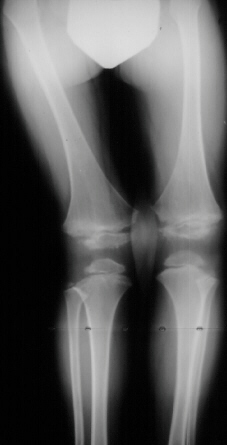

An 11 year old white male presented with a diagnosis of Multiple Epiphyseal Dysplasia (MED). Initially he presented with x-rays revealing mild genu valgum (image1) which progressed (image2) such that he required surgery. He had a supracondylar osteotomy which was performed in 1993 for genu valgum(image3). Two years later he was last seen for low back pain.